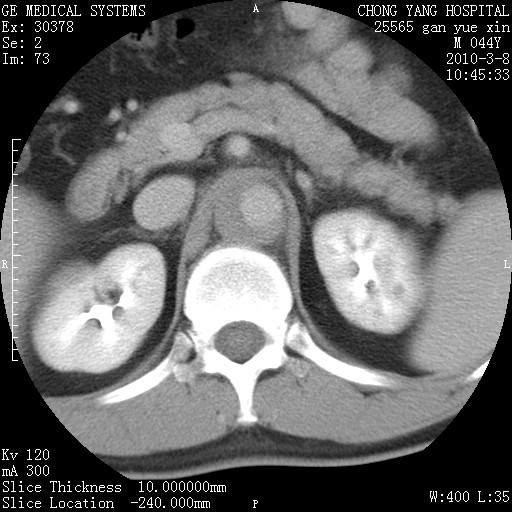

标题: CT24940:主动脉增强,典型病例。 [打印本页]

标题: CT24940:主动脉增强,典型病例。

夹层动脉瘤。

动脉夹层

夹层动脉瘤,典型

主动脉夹层。

动脉夹层的分型:

⒈debakey分型:根据主动脉夹层累及部位,分为三型:ⅰ型:原发破口位于升主动脉或主动脉弓部,夹层累及升主动脉、主动脉弓部、胸主动脉、腹主动脉大部或全部,少数可累及髂动脉。ⅱ型:原发破口位于升主动脉,夹层累及升主动脉,少数可累及部分主动脉弓。ⅲ型:原发破口位于左锁骨下动脉开口远端,根据夹层累及范围又分为ⅲa,ⅲb。ⅲa型:夹层累及胸主动脉。ⅲb型:夹层累及升主动脉、腹主动脉大部或全部。少数可累及髂动脉。

⒉stanford分型:a型:夹层累及升主动脉,无论远端范围如何。b型:夹层累及左锁骨下动脉开口以远的降主动脉。

夹层动脉瘤,少量胸水

夹层动脉瘤;左侧少量胸腔积液。

典型主动脉夹层。